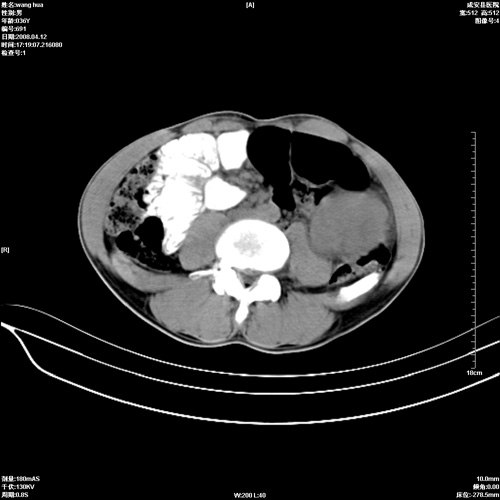

标题: CT12809:男36岁,自感上腹胀5天,B超诊断为脾肾之间占位,血 [打印本页]

标题: CT12809:男36岁,自感上腹胀5天,B超诊断为脾肾之间占位,血

请各位老师先分析一下定位 明天做增强

病变应该来源于脾脏,良性占位可能性大,不太象脾破裂,增强再说吧

脾脏明显增大,其内见巨大低密度灶,境界不清,病史较短,考虑恶性病变脾血管内皮细胞肉瘤可能。建议增强扫描与脾脏淋巴瘤及血管瘤鉴别。